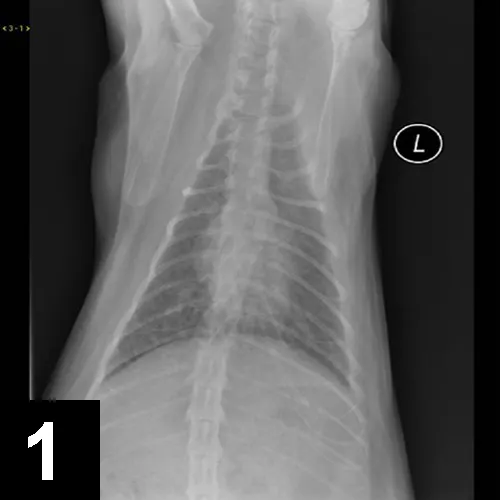

Parasite TestingLungworm and heartworm infections may cause similar signs. Lungworm infection, most common in young cats with exposure to outdoors and intermediate hosts, may cause clinical and radiographic signs

(Figure 3) similar to lower airway disease. Infection may be evaluated with a Baermann fecal sedimentation, or larva may be observed with airway cytology samples (Figure 4). Heartworm disease should be tested (via heartworm antigen and antibody test) in any cat with airway signs.

F__igure 3. Signs of lungworm infection that presented with signs similar to lower airway disease.